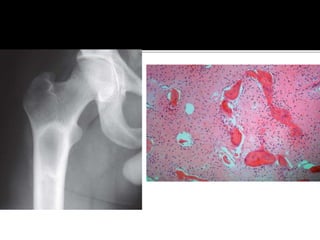

 Common in adults, M=F

 Can affect any bone

 Hyperparathyoridism

1 – Adenoma

2 – Patients with CRF

 Focal demineralization – “BrownTumor”

 Presentation – Asymptomatic, a/w

pathological fracture and symptoms of

hypercalcemia (nausea, vomiting, weakness,

headaches, generalized bone pain)

 Radiology – Diffuse osteopenia, multifocal

radiolucent lesions with surrounding reactive

bone

 Histology – Giant cells, increased osteoclastic

activity, marrow fibrosis.

 Diagnosis – S. Ca( ),P, ALP( ), PTH

 Medical Management – Secondary

Hyperparathyoridism –Treat CRF/VitD

deficiency

 Surgical Management – Parathyroid

adenoma excision

Treating actual/impending pathological

fractures